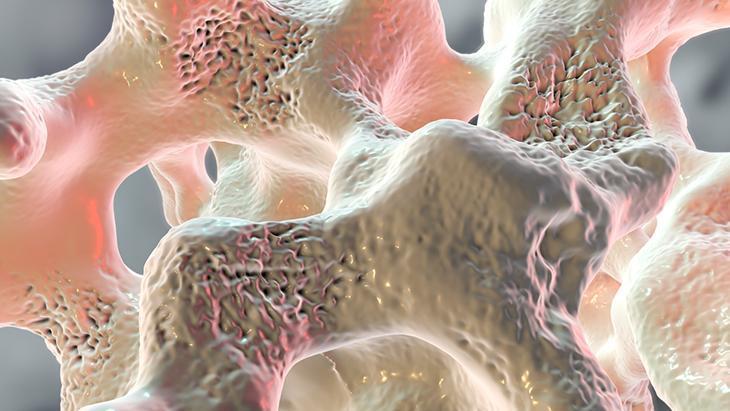

Kemik dokusunda ve kalitesinde bozulma olunca erimenin ortaya çıktığını belirten Dr. İlin, “Osteoporoz kemiklerde kırık riskini artırarak hem yaşam kalitesini düşüren hem de ölümle sonuçlanabilen komplikasyonlara yol açabilen ve kırık oluşana kadar sessiz seyreden bir hastalıktır. Kemik kırılganlığında artış her kadının yaşayacağı bir sorun olarak karşımıza çıkıyor.

Kemiklerin çok dinamik bir organ olduğunu söyleyen Uzm. Dr. İlin, normal kemik dokusunda sürekli ve dengeli bir şekilde yapım ve yıkımın söz konusu olduğunu söyledi. Doğumdan ergenliğe kadar şekillenip büyümeye devam eden kemik kütlesinin, ergenlikte doruğa ulaştığını söyleyen Uzm.Dr. İlin, bu dönemde sahip olunabilinecek güçlü kemik yapısı oranına paralel olarak ilerleyen yaşlarda osteoporoz gelişme riskinin azalacağını dile getirdi.